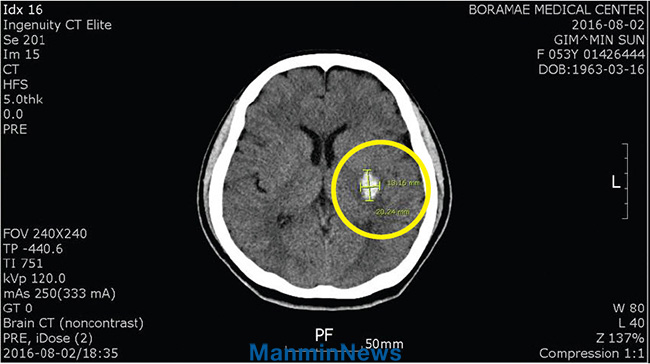

2016³â 7¿ù 31ÀÏ(ÁÖÀÏ), °©Àڱ⠱â¿îÀÌ Âß ºüÁö¸ç ¿À¸¥ÂÊ ¸öÀÇ °¨°¢ÀÌ ¾à°£ ¶³¾îÁø µíÇÑ ´À³¦ÀÌ µé¾ú½À´Ï´Ù. ½Ã°£ÀÌ ¿©ÀÇÄ¡ ¾Ê¾Æ 8¿ù 1ÀÏ(¿ù) ¹ã 11½Ã°æ¿¡¾ß È®ÀÎÂ÷ º¸¶ó¸Åº´¿ø ÀÀ±Þ½Ç¿¡ ã¾Æ°¬½À´Ï´Ù. CTÃÔ¿µ °á°ú, ³úÃâÇ÷À̾úÁö¿ä.

CTÃÔ¿µ

±âµµ¹Þ±â Àü ÁÂÃø ´ë³úÇÙ ºÎÀ§¿¡ 2 cm Å©±âÀÇ ÃâÇ÷ÀÌ º¸À̰í ÀÖÀ½.

±âµµ¹ÞÀº ÈÄ Ç÷Á¾ÀÌ »ç¶óÁü.